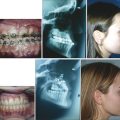

In cleft lip and palate, the defect extends along the junction of the primary and secondary palate, resulting in an alveolar gap. When the alveolus is cleft, lateral incisors are frequently absent and other dental anomalies, such as supernumerary teeth, are common. The palatal component of orofacial clefts is often described using the Veau classification (Fig. 15‑2).

Submucous cleft palate is a lesser form of cleft palate involving muscular diastasis of the soft palate, with intact palatal mucosa. The diastasis may be visualized as a bluish “zona pellucida,” or furrow, in the soft palate. Other findings may include a bifid uvula and/or a notch in the posterior hard palate (Fig. 15‑3). These three findings constitute Calnan’s triad. This type of cleft is often diagnosed during evaluation of abnormal speech.